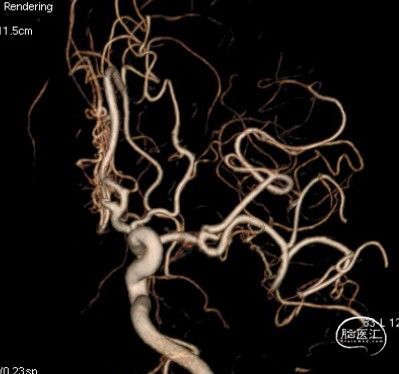

病人乙的影像资料:

MRA:双侧大脑中动脉、左侧大脑前动脉重度狭窄至闭塞

造影:右侧颈内动脉末段变细,右侧大脑中动脉M1段分叉前重度狭窄,豆纹动脉增多,右侧大脑前动脉向大脑中动脉分布区代偿供血:

三维重建显示右侧大脑中动脉分叉前部重度狭窄,狭窄段直径0.4mm,狭窄程度约84%:

左侧颈内动脉末段、大脑前动脉A1段、大脑中动脉M1段变细:

总结:在降压药降压的“加强试验”条件下,发现右侧为主的双侧三分叉部位狭窄,右侧大脑半球血流动力学相关腔梗。